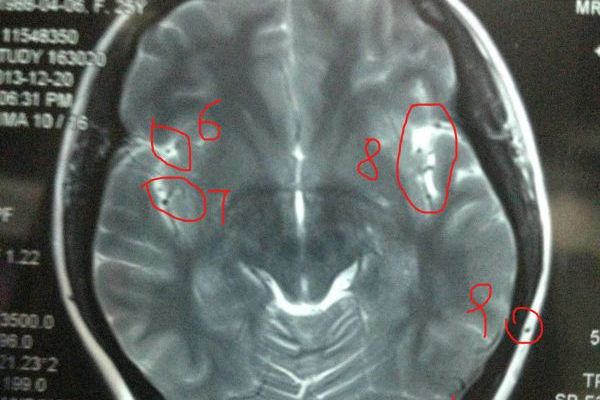

MR提供的信息量不仅大于医学成像中的许多其他成像技术,而且也不同于现有的成像技术。因此,它在疾病诊断方面具有很大的潜力。可直接制作断面、矢状面、冠状面及各种斜面的断层图像核磁共振仪价格,在CT检测中不产生伪影;无需注射造影剂;无电离辐射,对身体无不良影响。MR对脑内血肿、脑外血肿、脑肿瘤、颅内动脉瘤、动静脉血管畸形、脑缺血、椎管内肿瘤、脊髓空洞症、脊髓积水等常见脑部疾病的检测非常有效。对腰椎间盘突出症的诊断也非常有效,